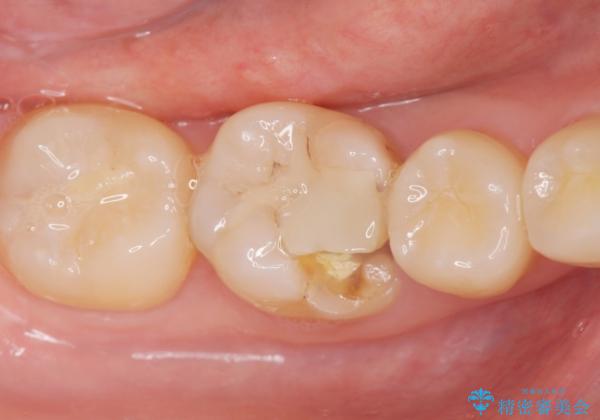

- 過去に退院で治療した詰め物が欠けたことにより来院。

古いプラスチックの樹脂、虫歯を全て取り除き

ジルコニアクラウンにて治療しました。